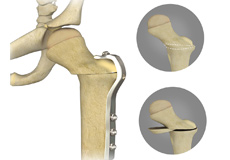

Femoral Osteotomy

Femoral derotational osteotomy (FDO) is a surgical procedure employed for the treatment of femoral torsion and a damaged/dislocated hip joint due to spasticity in children and adults. Femoral torsion is an inward turning of the femur (thigh bone) at the hip which causes an individual’s knees and feet to turn inward giving a pigeon-toed appearance.